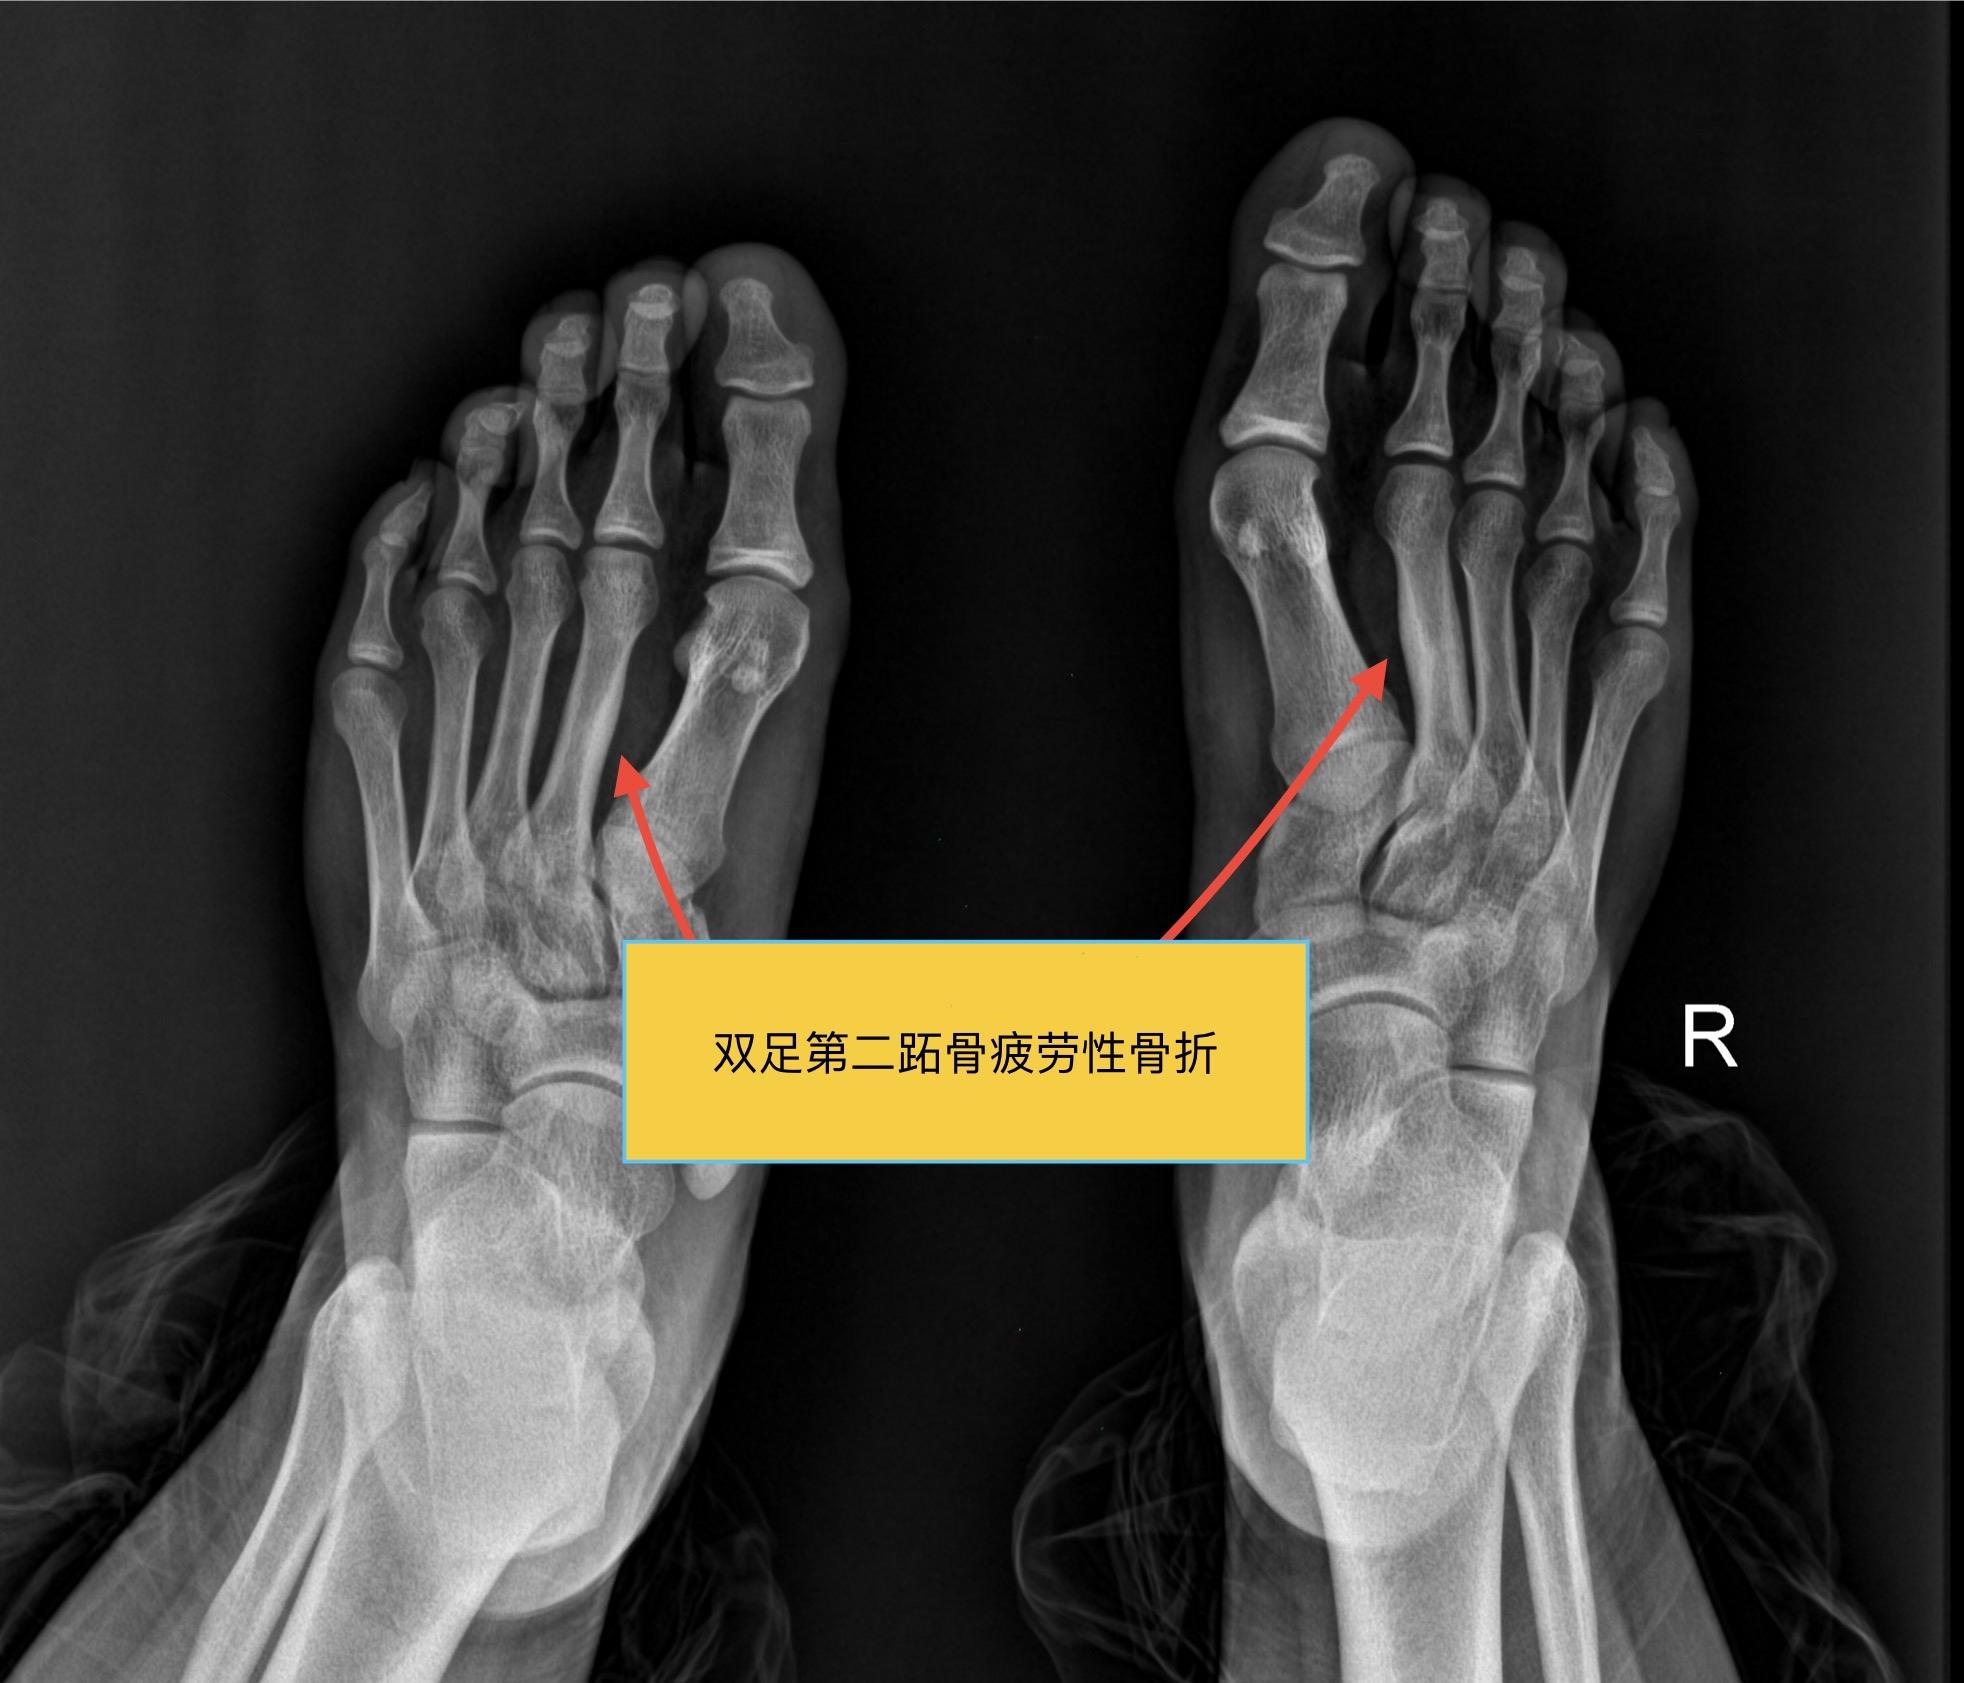

【骨肌】爱运动的烦恼!男,15岁,双侧足底部隐痛,爱好运动,喜欢长跑与打羽毛球!

男,15岁,双侧足底部隐痛,爱好运动,喜欢长跑与打羽毛球!